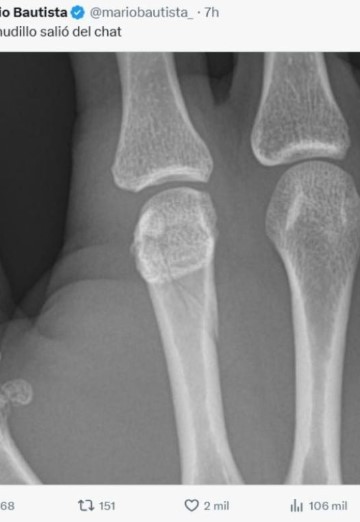

Y es que después del evento Mario Bautista compartió una imagen de una radiografía de su mano derecha en la que mostró que había sufrido una fractura.

En la imagen se podía ver una fractura en su dedo, una lesión que es muy común entre los boxeadores debido a que esta lesión se presenta debajo de la cabeza del hueso, por lo que es llamada por los profesionales como la “fractura del boxeador”.